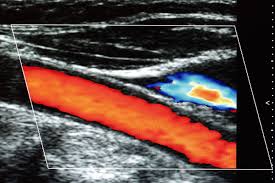

颈动脉是人体通向头部血管的主要动脉,提供大脑85%的血液供应,在动脉粥样硬化的发生发展过程中,颈动脉是最易受累的部位。颈动脉是全身动脉血管中最表浅的大动脉,利用二维超声及彩色多普勒相结合的超声技术,可清晰地观察颈动脉内部状态。

颈动脉超声检查简便无创、价格低廉、重复性好,患者易于接受,作为一种无创性检查手段可观察早期动脉粥样硬化病变,既能定量地测量颈动脉内中膜厚度(IMT)的结构变化从而了解心脑血管粥样硬化存在的严重程度,又能在诊断颈动脉粥样硬化斑块时清晰地显示斑块特征和血流动力学情况。

③颈动脉血管狭窄:说明颈动脉粥样硬化已发展到较严重的阶段,斑块影响了颈动脉的血流。